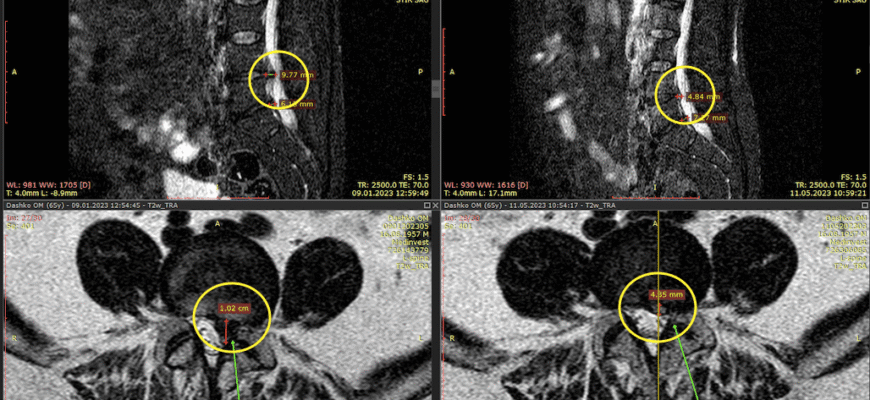

| МРТ | Шукає зміни в м’яких тканинах |